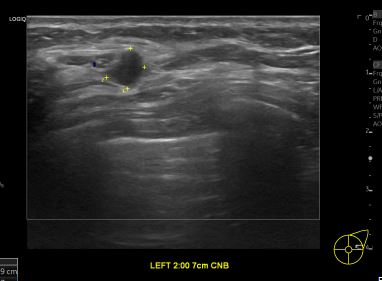

상기환자 외부검사이상으로 정밀검사위해 내원하신 60대 여성분으로

좌측유방 혹 총조직검사 시행해 유방암 진단되었습니다.